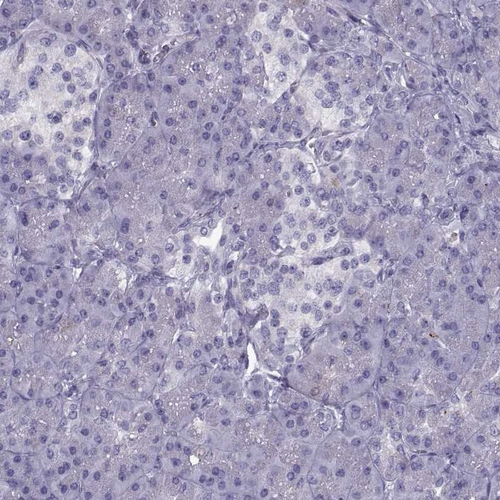

Immunohistochemical staining of human cerebral cortex, hypothalamus, lymphoid tissues and pancreas using Anti-CALCR antibody HPA028962 (A) shows similar protein distribution across tissues to independent antibody HPA061428 (B).